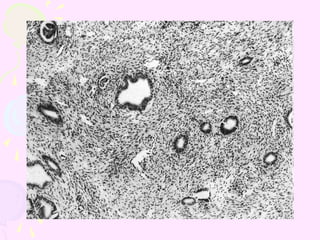

• #3 Benign endometrial glands without architectural complexity or cytologic atypia are surrounded by stroma that consists predominantly of smooth muscle. This lesion presented as a polyp projecting into the endometrial cavity.